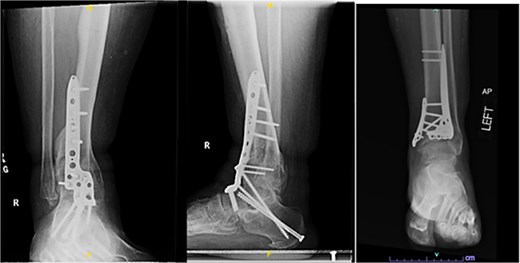

One year after the initial surgery, the left leg healed without any complications. However, the right leg developed nonunion through the distal tibia, along with posttraumatic arthritis. As a result, the patient underwent a right ankle fusion. Additionally, 2.5 years after the index surgery (1.5 years after the ankle fusion), the patient required removal of the right lateral fibular plate due to painful hardware. Six months later (3 years post-index surgery), the patient then underwent subtalar fusion due to post-traumatic arthropathy and ongoing pain (Fig. 2).

Radiographs of patient 1 obtained 3 years after the index procedure, including AP view of the left ankle and lateral and oblique views of the right ankle following subtalar fusion.